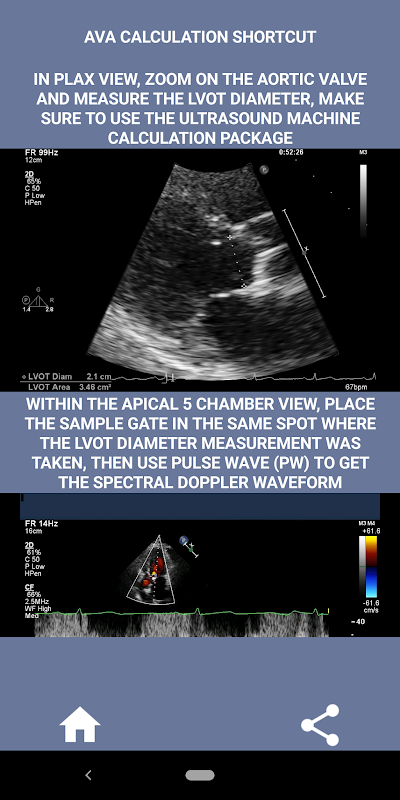

A mio parere, se un intervistato può dimostrare con forza questa abilità quella persona ha un enorme vantaggio rispetto agli altri candidati che sono deboli in quest'area (è logico perché normalmente ci sono così tanti casi di stenosi aortica). Se stai facendo domanda per una posizione di ecografista cardiaco, qualcuno che ha solo bisogno di rinfrescare le sue abilità o uno studente di eco, allora questa app è stata progettata pensando a te da un ecografista cardiaco attualmente praticante. Semplice e breve, dritto al punto con molti video illustrativi che indicano esattamente dove misurare (ad es. diametro LVOT) e come misurare secondo le linee guida ASE/ICAEL pubblicate.